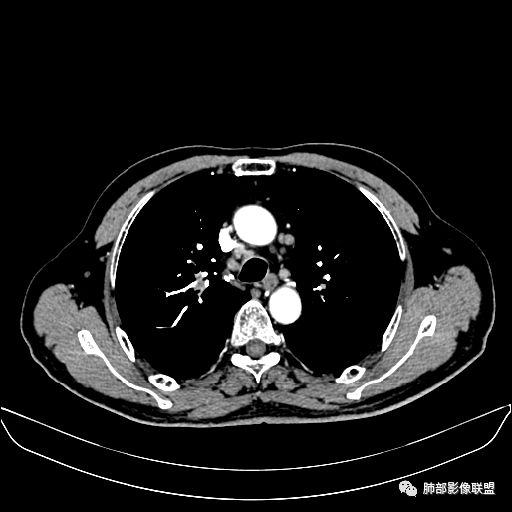

住院4天后行胸部增强CT

静脉期

淋巴结肿大,钙化。

但是钙化,密度高,没有融合,平扫没有坏死

肺门纵隔多发淋巴结肿大,内有钙化灶

吴婧老师和南边老师都对该病例进行了深入分析。从支气管管壁的增厚,支气管狭窄后扩张,支气管粘液栓,病灶形态,到病灶不均匀强化及坏死彻底,到周边病灶及肺组织空气的潴留,加之纵隔内淋巴结肿大伴钙化等等,都支持慢性炎性病灶,尤其是结核。

墨西哥仙人掌征---结核        影像上结核灶,粗大的均匀枝干,推测是支气管囊状扩张引起的,在非支气管区,形成圆形坏死囊群;如果这些坏死比较稀薄,又遇到扩张支气管,就会形成粗大的“墨西哥仙人掌”。结核引起的支气管近端炎症纤维化,可以造成支气管阻塞,从而将干酪样坏死物封堵在管腔内。仙人掌主干内部应该是干酪为主,稀薄的,具有流动性,时间久了会出现钙化。

结核坏死与鳞癌鉴别有一点是结核坏死没有方向性,鳞癌有。鳞癌靠近支气管近端部分,血供容易维持,不易坏死,所以坏死靠外侧。而结核干酪样坏死,把一定体积的流动性坏死物,包裹起来,什么形状最省料?坏死物包裹,表面积最省的自然是圆球形,而遇到支气管,坏死物一多,就把支气管撑大了。包裹物是就地取材,扩张的支气管就成了包裹结构。